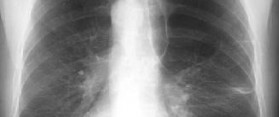

How to Join a Drug Trial for Emphysema

– Image courtesy: virtualmedicalcentre.com